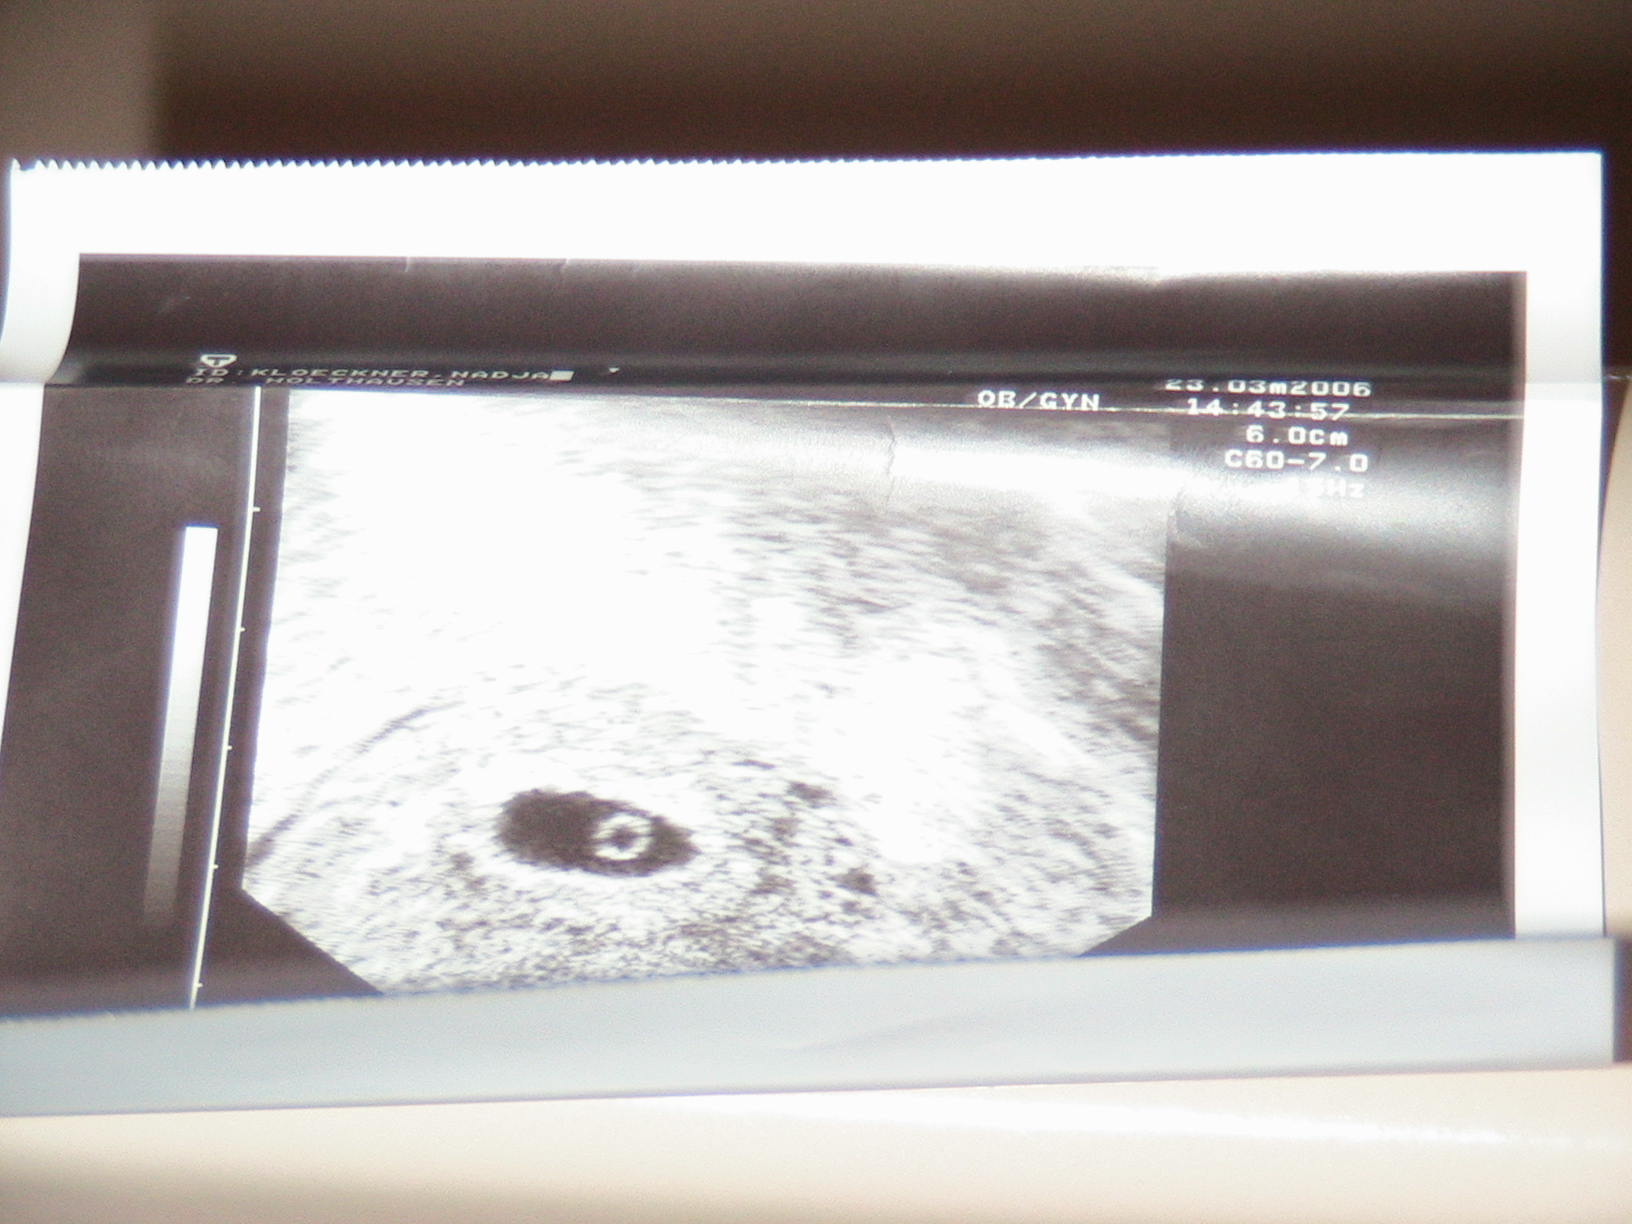

Der Doc hat mir noch kein Blut abgenommen das wurde nur im Krankenhaus gemacht ich warte einfach mal bis nächste Woche Donnerstag ab dann werde ich es ja sehen.der Dottersack ist doch normall Ovall oder?

Ich habe auch Dr Peet gefragt er sagte mir nächste Woche sieht mal SchlumpiTigerchen:-) hat geschrieben:die Form des Dottersacks ist eigentlich egal. Habe damals aber diesbezüglich auch Dr. Peet gefragt. Man reagiert, ja auf alles viel empfindlicher als sonst, aber das ist ja eigentlich ein gutes Zeichen, wenn die Hormone so zuverlässig sind![]()